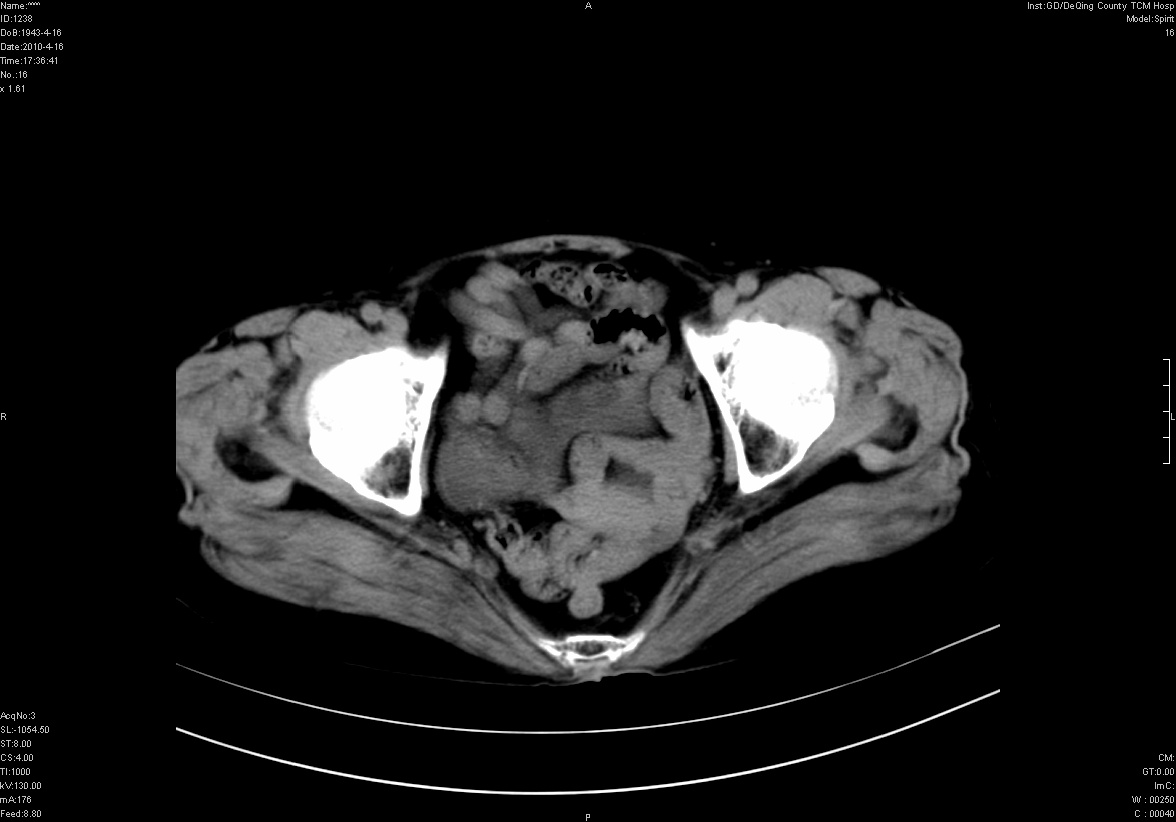

标题: CT25796:女,60岁,腹痛5天,请会诊??? [打印本页]

标题: CT25796:女,60岁,腹痛5天,请会诊???

考虑卵巢畸胎瘤。

支持右侧盆腔畸胎瘤。

右侧附件畸胎瘤

考虑右侧卵巢畸胎瘤。

考虑右侧卵巢畸胎瘤

右侧卵巢畸胎瘤可能。